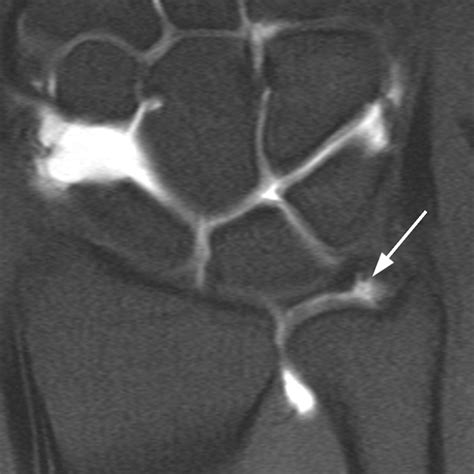

• Imaging Tests: X-rays can rule out fractures or other bone abnormalities. Magnetic Resonance Imaging (MRI) or Magnetic Resonance Arthrography (MRA) can provide detailed images of the soft tissues, including the TFCC.

• triangular fibrocartilage tear mri

• triangular fibrocartilage tear radiology